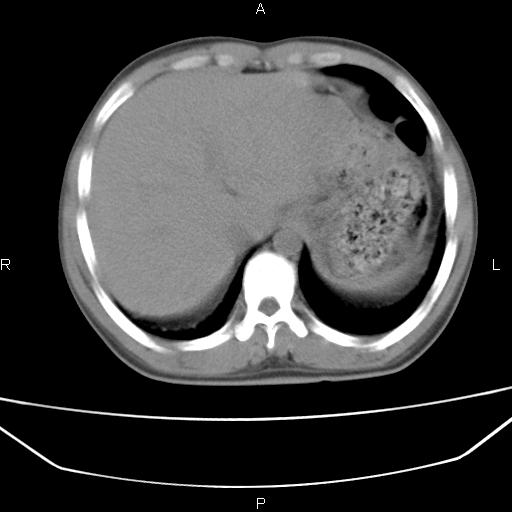

患者,男,40岁。间断发热,咳嗽二十余日。体温最高达38.9° 在当地诊所抗炎治疗三天后体温降至正常,患者自行停药。今又发热。胸片示,左下肺阴影。

左下肺片状高密度影,境界模糊,密度不均,考虑感染性病变可能性大,建议抗炎治疗后复查。左肺门增大,不除外占位性病变,必要时支气管镜检。